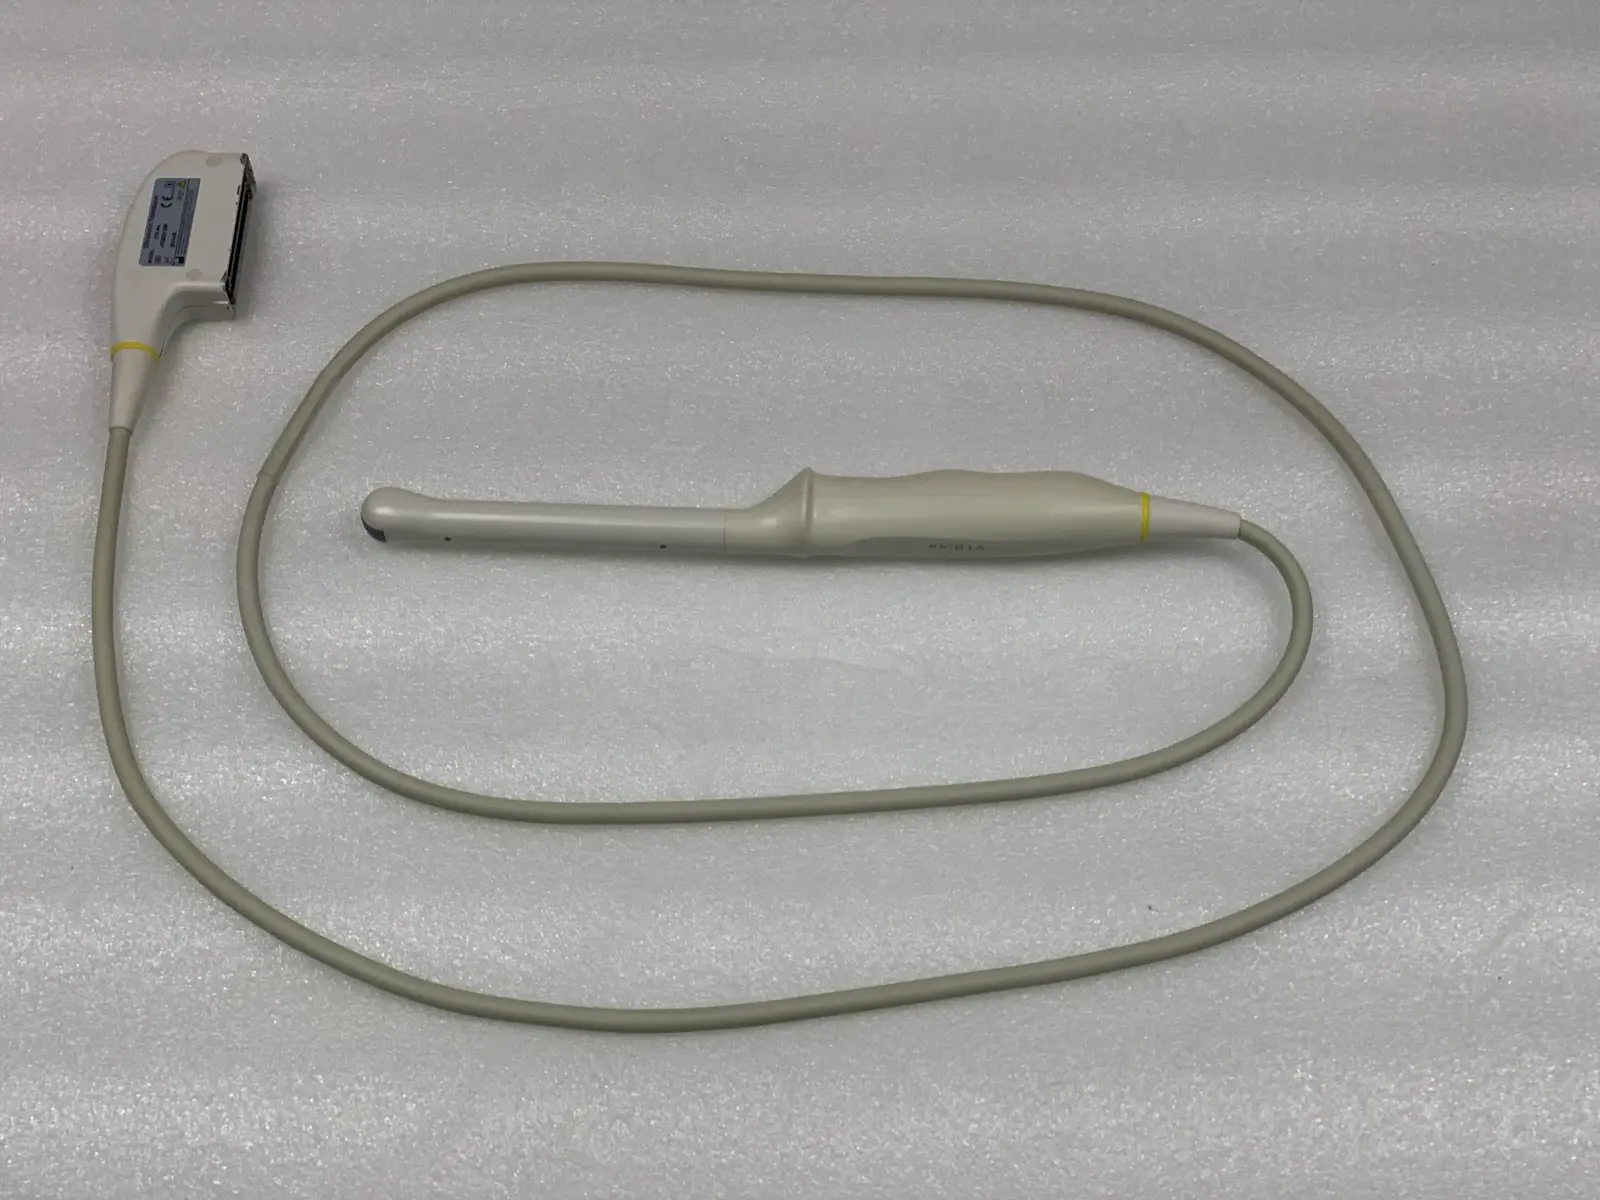

Condition: Used, working

Brand: Mindray

Model: V10-4s

MPN: 023-000041-00

Probe Type: Endocavity / Transvaginal / Micro-convex

Frequency Range: 4.0 MHz – 10.0 MHz

Compatibility: Mindray M7, M7 Premium, M7 Expert, M6 series

Applications: OB/GYN, Urology, Veterinary

Up for sale is a genuine Mindray V10-4s curved array endocavity probe. This transducer is designed for high-resolution imaging in obstetrics, gynecology, and urology. It features a wide-band frequency range (4–10 MHz) and a small 10mm radius for patient comfort.

Acoustic Window (Lens): Appears clean and intact with no significant delamination or pitting visible in photos.

Cable & Connector: The cable is flexible without exposed shielding; the connector pins are straight and the locking lever is functional.

Source: Removed from a clinical environment. The probe was tested on a Mindray MR-M7 Ultrasound unit to confirm full functionality, image quality, and connectivity.

Blemish : Some cosmetic blemishes

Photos of this listing are of the actual item for sale.